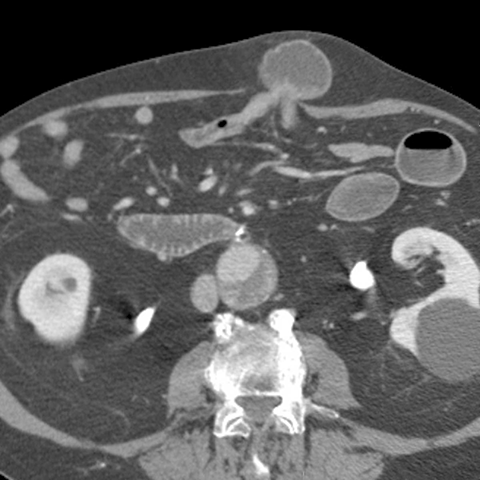

66 year-old male presents with a protruding abdominal mass and pain. [1 of 2]